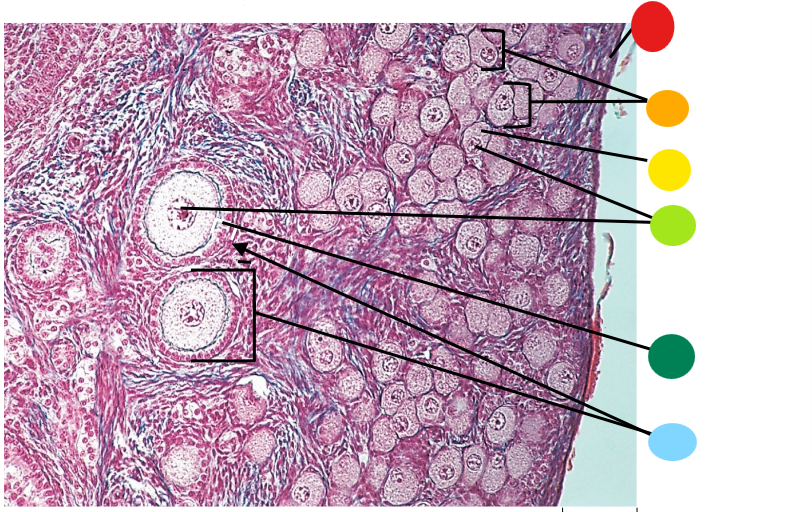

Lab H: Female reproductive histology

red

tunica albuginea

orange

primordial follicles

yellow

follicular cells

light green

primary oocyte

dark green

granulosa cells

light blue

primary follicles

what is this?

ovary